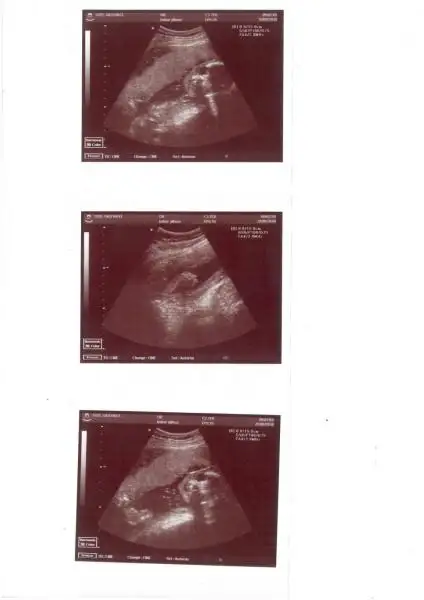

yaaa kızııım 4 boyutlu bilmonmu?? hani 3 boyutlu ultrasona giriyosun bi yandanda kalp atışlarını dinnosun doppler cihazına bağlıyolar ya. ööle oluyo işte. çok heyecan verici bişi. Eki Görüntüle 54286

aneaaaaammmm yir onu teyzesiiihıııı 4 boyutlu dene şey bu ıse ben bu son gıttığımde yaptrdım bebişime onuuu... elbette çok heyecan verıcııı işaret parmağını ağzına goturup durdu benım oğlum kalbı de maşallah nasıl atıooodr bey bıle maşallah çok şirin hareketler yapıor demiştiii

hıııı 4 boyutlu dene şey bu ıse ben bu son gıttığımde yaptrdım bebişime onuuu... elbette çok heyecan verıcııı işaret parmağını ağzına goturup durdu benım oğlum kalbı de maşallah nasıl atıooodr bey bıle maşallah çok şirin hareketler yapıor demiştiii